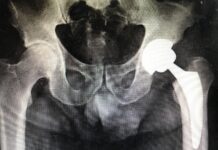

Artrosi dell’Anca o Coxartrosi

Il movimento è vita, la vita è movimento

Sembrerebbe una banale battuta ma è un’incontrovertibile verità. L’essere umano si muove, si sposta, si piega, si...